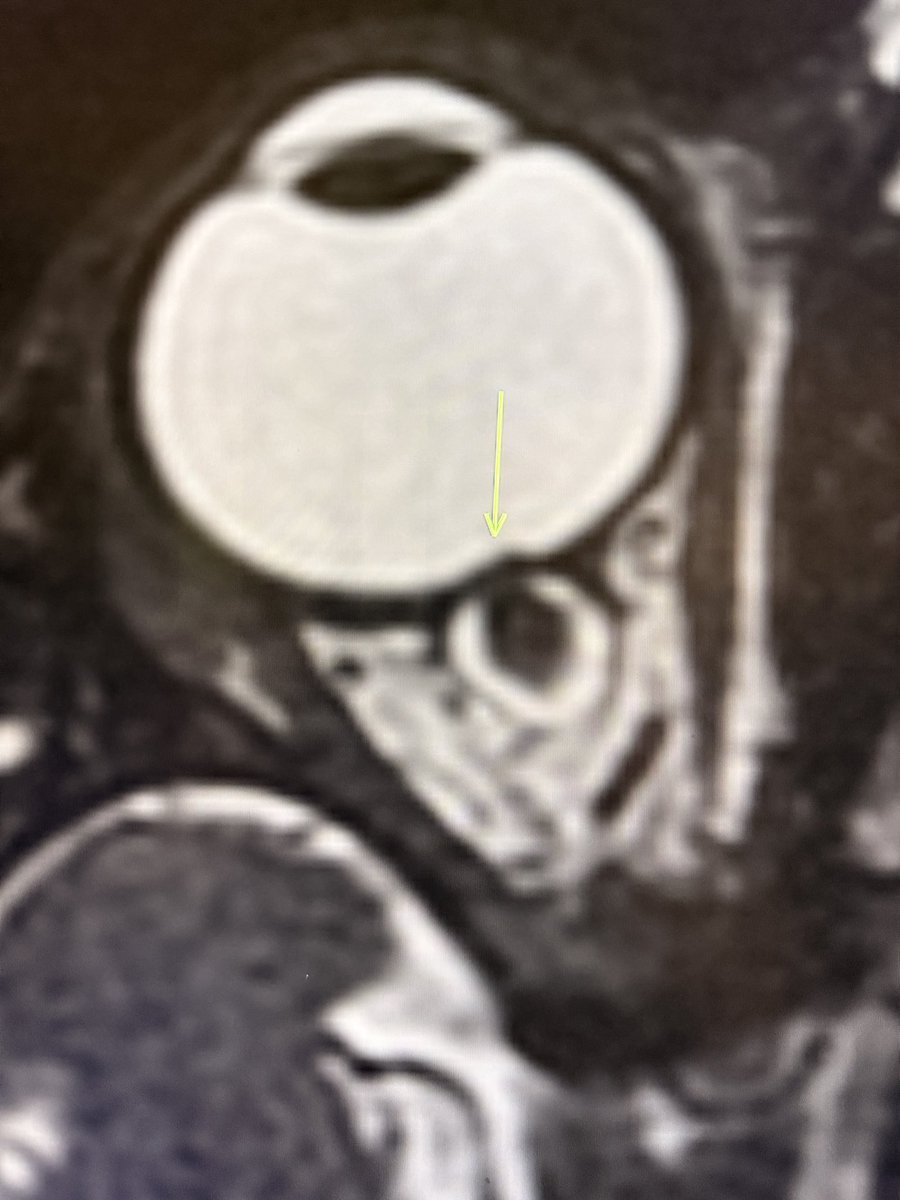

Nothing fancy today! Just a classic case of papilledema on MRI: 1. Flattened posterior sclera 2. Protrusion of the optic nerve head (bulging into the globe) —Classic signs from my reporting list

Nothing fancy today!

Just a classic case of papilledema on MRI:

1. Flattened posterior sclera

2. Protrusion of the optic nerve head (bulging into the globe)

—Classic signs from my reporting list